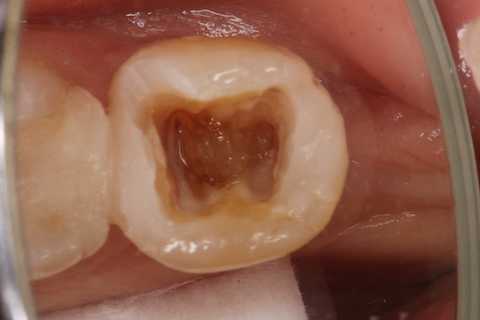

30代女性、左下7、Per、動揺度2.5

今日の症例は8年前に僕が親知らずが遠心に食い込んで虫歯になったものを神経を取らずにCR充填したものだが、とうとう接着剥がれが起こり神経が死んでしまった。神経は全く残っておらず。溶けてなくなっていた。

この症例は歯根内部をいじられていないので、根管治療は難しくない。CRで歯冠を再建するのが難しかった。